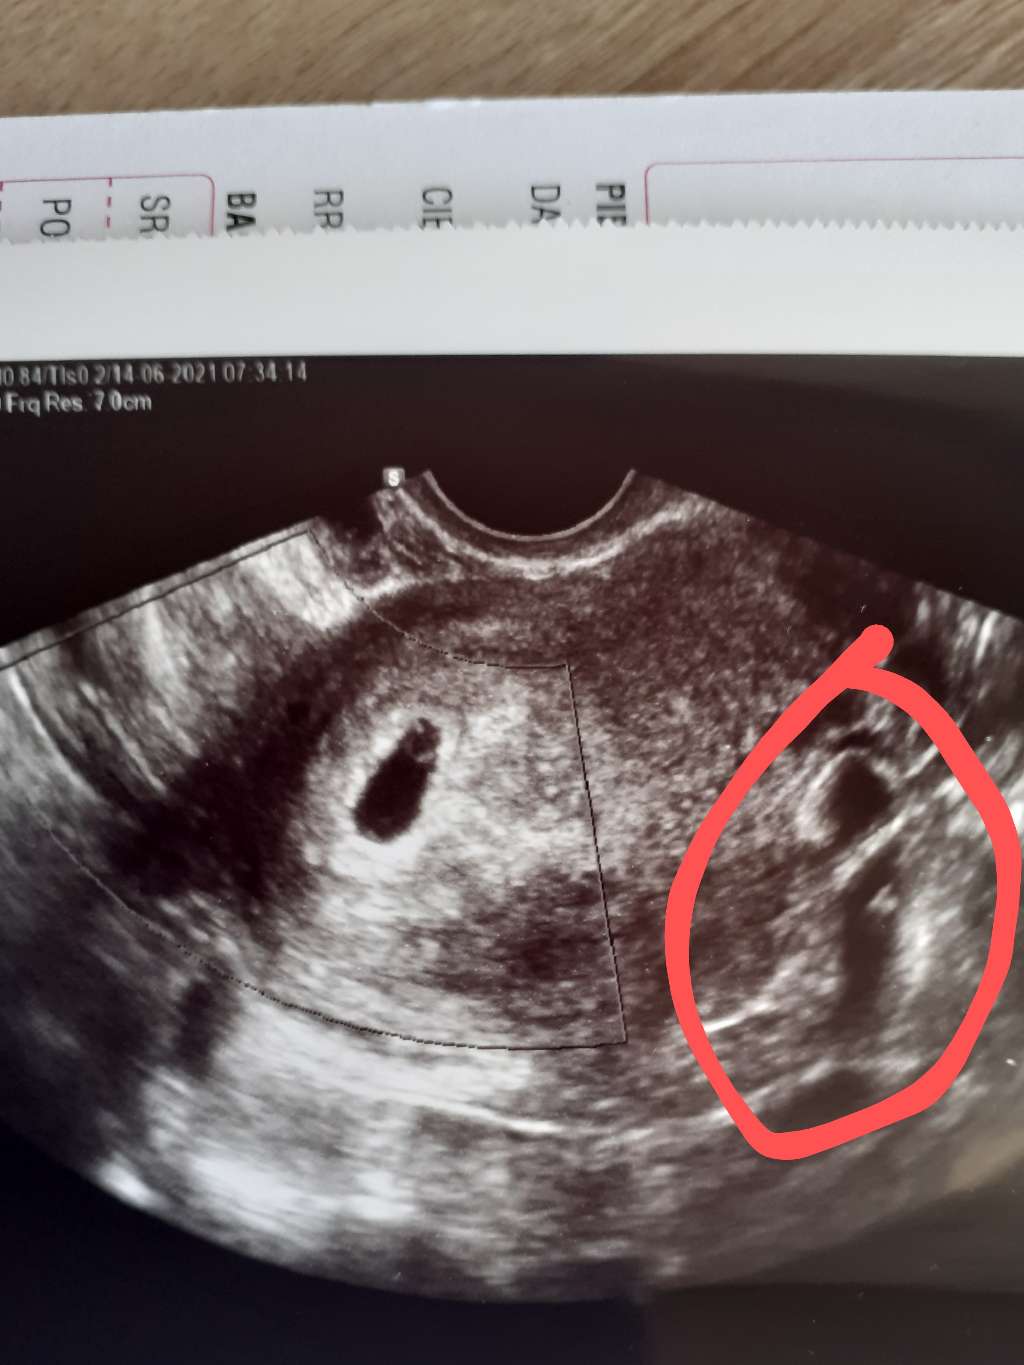

Wrzucę jeszcze raz ,.bo kurde siostra,mama,bratowa i szwagierka

Najblizsze osoby, które wiedzą i którym pokazałam zdjęcie i one wszystkie twierdza że są dwa

A Ja tak bylam wpatrzona w pęcherzyk że nawet nie zauważyłam że tam coś jeszcze jest

Jeszcze siostra mi powiedziała że lekarz się zawsze mówi od razu bo jeden z pęcherzyków lubi się wchłonąć

Napiszcie co myślicie, bo zwarjuje do 5 lipca

Chodź mi o to zaznaczone, bo tamto drugie to napreno pęcherzyk